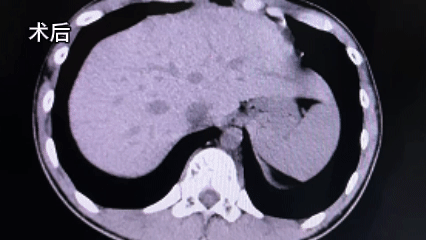

这一灵活的战术调整立竿见影。软镜凭借其可弯曲的优势,顺利到达了肾镜无法触及的肾中上盏区域,精准地锁定了结石。在清晰的可视化操作下,顺利完成碎石取石操作。整个手术过程出血量少,未对周围组织器官造成副损伤。

术后恢复良好

在医护团队的精心照护下,术后患者病情平稳,逐步康复。此次经皮肾镜+软镜双结合手术的成功,是我院外科团队针对复杂病例开展个体化诊疗的一次实践,也彰显了我院外科团队面对突发情况时灵活应变、以患者安全为核心、敢于优化方案的担当精神。我院将继续秉承精益求精的工匠精神,不断提升医疗技术和服务水平,为更多患者的健康保驾护航。